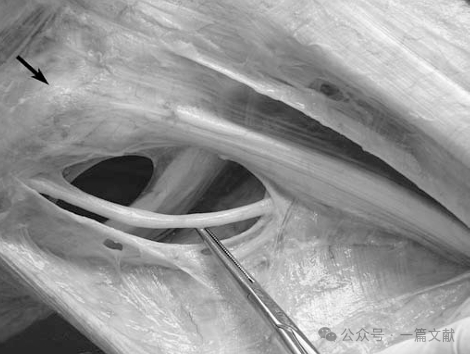

关节镜下腘肌腱走行:当腘肌腱穿行至腘肌裂孔时,通过前下、后上及后下三组腘肌半月板束附着于外侧半月板。这些半月板束形成"轮箍样"结构,将腘肌腱与腘肌裂孔处的外侧半月板紧密连接。